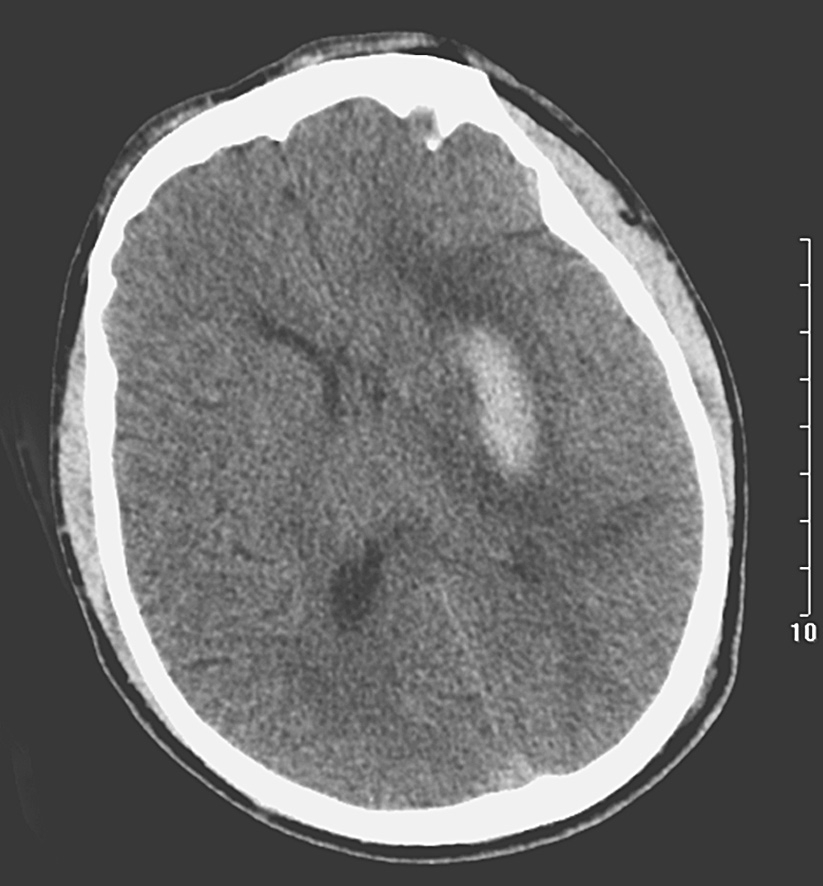

亚急性脑出血是指脑出血后3~14天时间内形成的出血性病变。CT检查显示血肿密度逐渐降低,每日下降约1.5Hu,可出现下列征象:①血肿周边吸收呈融冰样(图1-28),中心密度不变仍呈高密度。②占位效应和灶周水肿由明显而逐步减轻。③部分可出现脑积水。④增强扫描,病灶呈现环形或梭形强化,若中央部分血肿未吸收时,可呈“靶征”。

图1-28 亚急性脑出血

与图1-27为同一患者,CT平扫示左侧基底核血肿周围吸收呈融冰样,中心仍为高密度区,灶周仍为低密度水肿带,可见占位效应